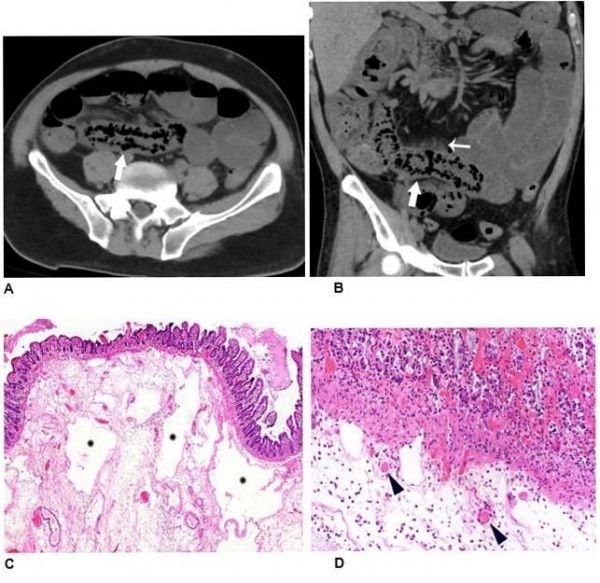

Image: Non-contrast axial (A) and coronal (B) CT performed in a 54-year-old man demonstrates pneumatosis cystoides intestinalis (arrows) in a long segment of ileum. Adjacent mesenteric congestion is also noted (thin arrow). Laparotomy demonstrated no frank bowel necrosis. Low power photomicrograph (H and E, 40x) of the ileum (C) shows ischemic degenerative changes of the mucosa with villous blunting (left) and withered crypts. There is marked submucosal edema with large empty spaces consistent with pneumatosis (*). High power view (H and E, 400x) (D) of the superficial submucosa shows arterioles with fibrin thrombi (arrowheads) beneath the damaged mucosa. (Credit: Radiological Society of North America)